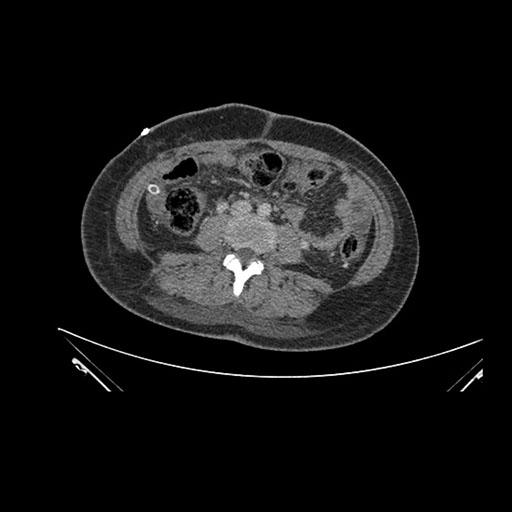

Imaging Analysis

Look through the patient's CT scan to identify any areas of concern for the necessary procedure.

Axial Arterial